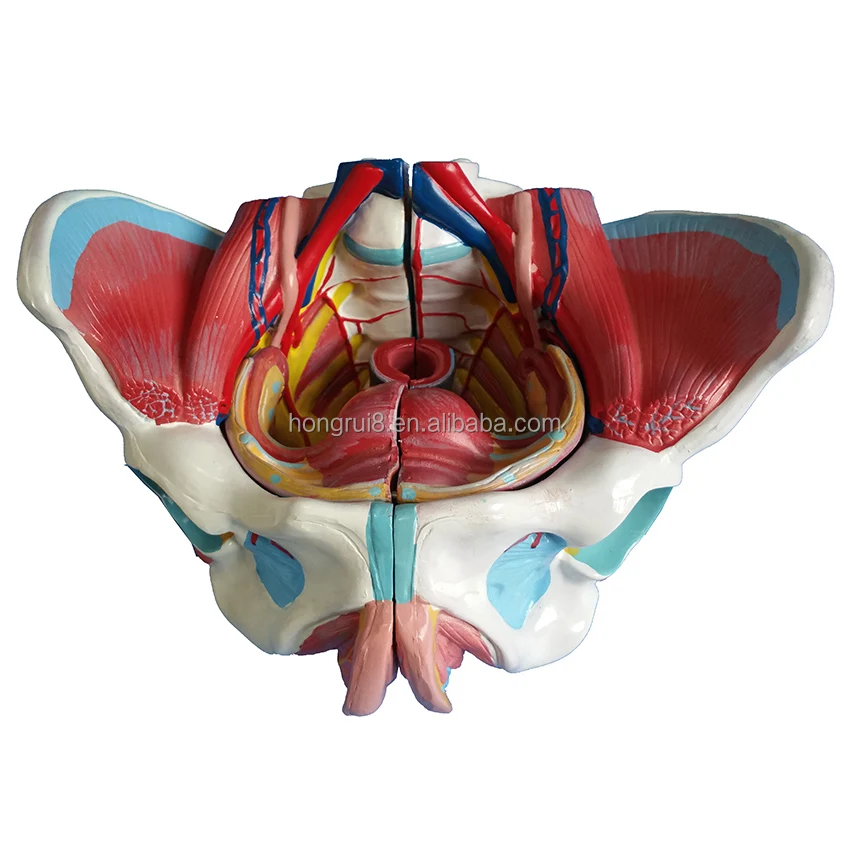

楽天ブックス: 骨盤帯原著第4版 - 臨床の専門的技能とリサーチの, 人間の臓器/骨盤骨格のモデル解剖学的モデル盆地腰椎椎骨 2,

人間の臓器/骨盤骨格のモデル解剖学的モデル盆地腰椎椎骨 2, ゴア® TAG® コンフォーマブル 胸部大動脈ステントグラフト骨盤帯 原著第4版臨床の専門的技能とリサーチの統合内容紹介●骨盤帯を中心に腰椎から股関節にかけての機能解剖とバイオメカニズム・疾患メカニズムと,その治療から予防までを具体的に解説した画期的な臨床書.●豊富な図説(3D模型や解剖図)と臨床写真(MRI,超音波画像を含む)は,読むものにとって理解を深めるための役立つツールであるご覧いただきありがとうございます。薬剤師国家試験回数別 第100回〜109回(102回以外)。\r書き込み、マーカー等はありません。ペイント番長直伝! 最薄で最大の成果を出す表面ステインテクニック。\r自宅保管をしていましたので、神経質な方はご遠慮ください。診察ができる vol.2 鑑別診断 第1版。返品はお受け致しかねますのでご了承下さい。獣医解剖学 : カラーアトラス 上巻。

ゴア® TAG® コンフォーマブル 胸部大動脈ステントグラフト骨盤帯 原著第4版臨床の専門的技能とリサーチの統合内容紹介●骨盤帯を中心に腰椎から股関節にかけての機能解剖とバイオメカニズム・疾患メカニズムと,その治療から予防までを具体的に解説した画期的な臨床書.●豊富な図説(3D模型や解剖図)と臨床写真(MRI,超音波画像を含む)は,読むものにとって理解を深めるための役立つツールであるご覧いただきありがとうございます。薬剤師国家試験回数別 第100回〜109回(102回以外)。\r書き込み、マーカー等はありません。ペイント番長直伝! 最薄で最大の成果を出す表面ステインテクニック。\r自宅保管をしていましたので、神経質な方はご遠慮ください。診察ができる vol.2 鑑別診断 第1版。返品はお受け致しかねますのでご了承下さい。獣医解剖学 : カラーアトラス 上巻。